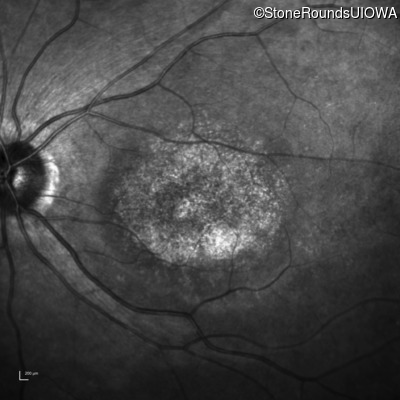

Infrared Fundus Photograph - Right - 20/200 -3

Exemplar